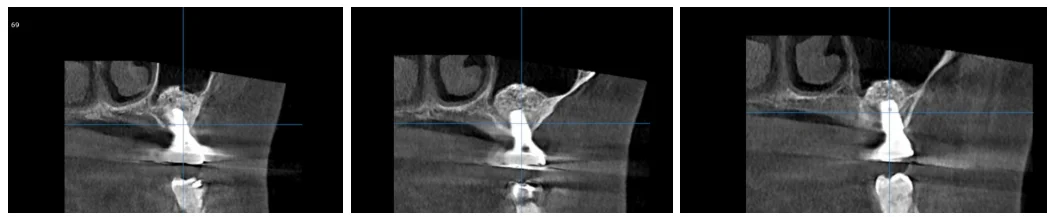

3차원 CT 촬영을 통해 확인한 결과, 이전 파노라마 사진보다 뼈의 양이 눈에 띄게 적게 보였습니다.

그럼에도 불구하고, 임플란트를 진행하는 데 지장을 줄 정도는 아니었습니다.

임플란트의 상부 톱니 부분이 골 속에서 안정적으로 자리 잡고 있는 것을 확인할 수 있었고, 뼈이식 부위 역시 잘 유지되고 있었습니다.